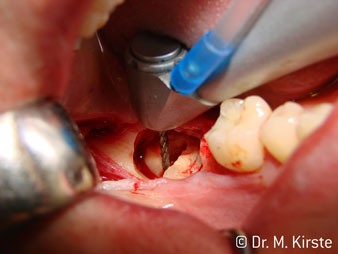

Le contre-angle avec tête angulée à 45° a surtout été choisi pour ses nombreux avantages. Les collègues qui exercent en chirurgie, et à qui cet instrument est principalement destiné, apprécieront très vite la possibilité de travailler efficacement dans des zones très étroites. En particulier, lors d’extractions de dent de sagesse (Ill. 2), où il n'y a pas besoin d’un grand angle d’écartement des tissus mous dans la région de la joue (Ill. 3). Pendant la préparation, une légère rotation de la tête de l’instrument permet un travail rapide et sans risque dans la zone rétromolaire.

En terme de rapidité, l'instrument peut atteindre jusqu’à 100 000 tr/min. Tandis qu'un spray très professionnel et une tête aux dimensions réduites répondent à toutes les exigences en matière de refroidissement et de visibilité de la zone de traitement.

La conception particulière des roulements à l'intérieur de la tête du contre-angle garantit un fonctionnement silencieux de l’instrument rotatif et lui procure une grande efficacité de coupe, sans à-coup ; ce qui est appréciable lors des interventions chirurgicales comme par exemple les séparations dentaires et résections apicales (Ill. 4-9).

Le contre-angle avec tête angulée à 45° est très agréable à utiliser. D’emblée on remarque que la partie travaillante de la tête imite l'angle de l’index et qu’ainsi le mouvement que vous souhaitez faire est simplement déplacé de deux ou trois centimètres, parallèlement à la pointe de l’instrument rotatif.“ (Ill. 1)